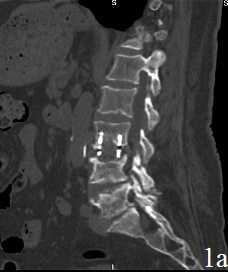

Рис. 1. Пациент В. Титановая блок-решетка без наполнения через 1 месяц (А) и через 12 месяцев (Б) после операции. Нарастание «продавливания» имплантатом кости с увеличением перифокального склероза и резорбции костной ткани

К концу первого месяца после операции (табл. 2) в обеих группах с одинаковой частотой выявлены умеренные реактивные изменения паравертебральных тканей при отсутствии признаков прогрессирования костной деструкции. Вместе с тем, в группе 1 у всех пациентов обнаружено “продавливание” меша в тела блокируемых позвонков на глубину до 1 мм и наличие перифокальной резорбции с отграниченной зоной склероза. В трети случаев у пациентов этой группы угол кифоза увеличился на величину более 5 ° , что не может быть расценено как ошибка измерения. В группе 2 - во всех случаях имплантат плотно соприкасался с телами позвонков без перифокальной резорбции и без нарастания деформации; склеротическая реакция блокируемых тел отмечена у 2 пациентов (8,7%).